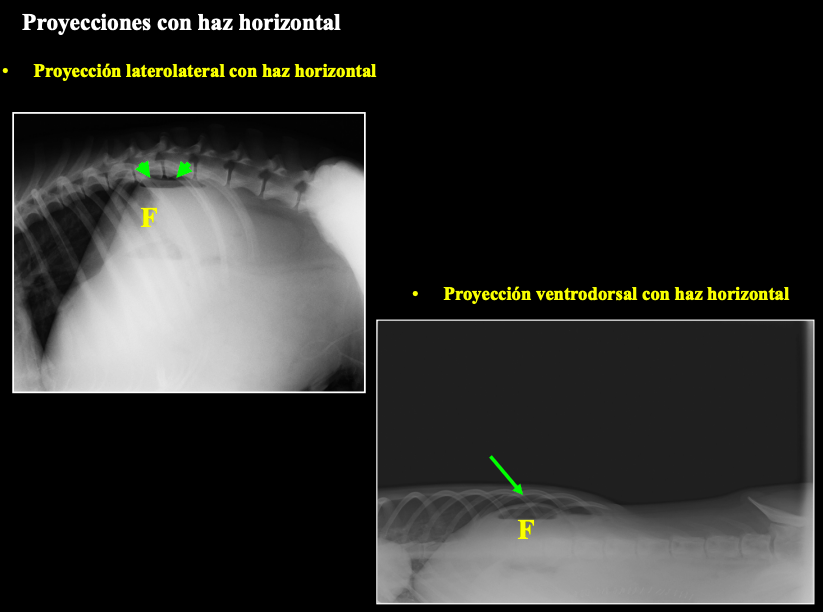

Proyecciones con haz horizontal. A veces por rotura de intestino o problemas hiatrogenicos (rotura del utero por fallo quirurgico)

Se ve una linea radio lucida craneal al higado por presencia de aire. Es bastante patognomonico. Tambien burbujas dorsales encima del higado, pegado al fundus

Proyecciones con haz horizontal

LL + haz horizontal

VD + haz horizontal

(F– marcados en imagen.)